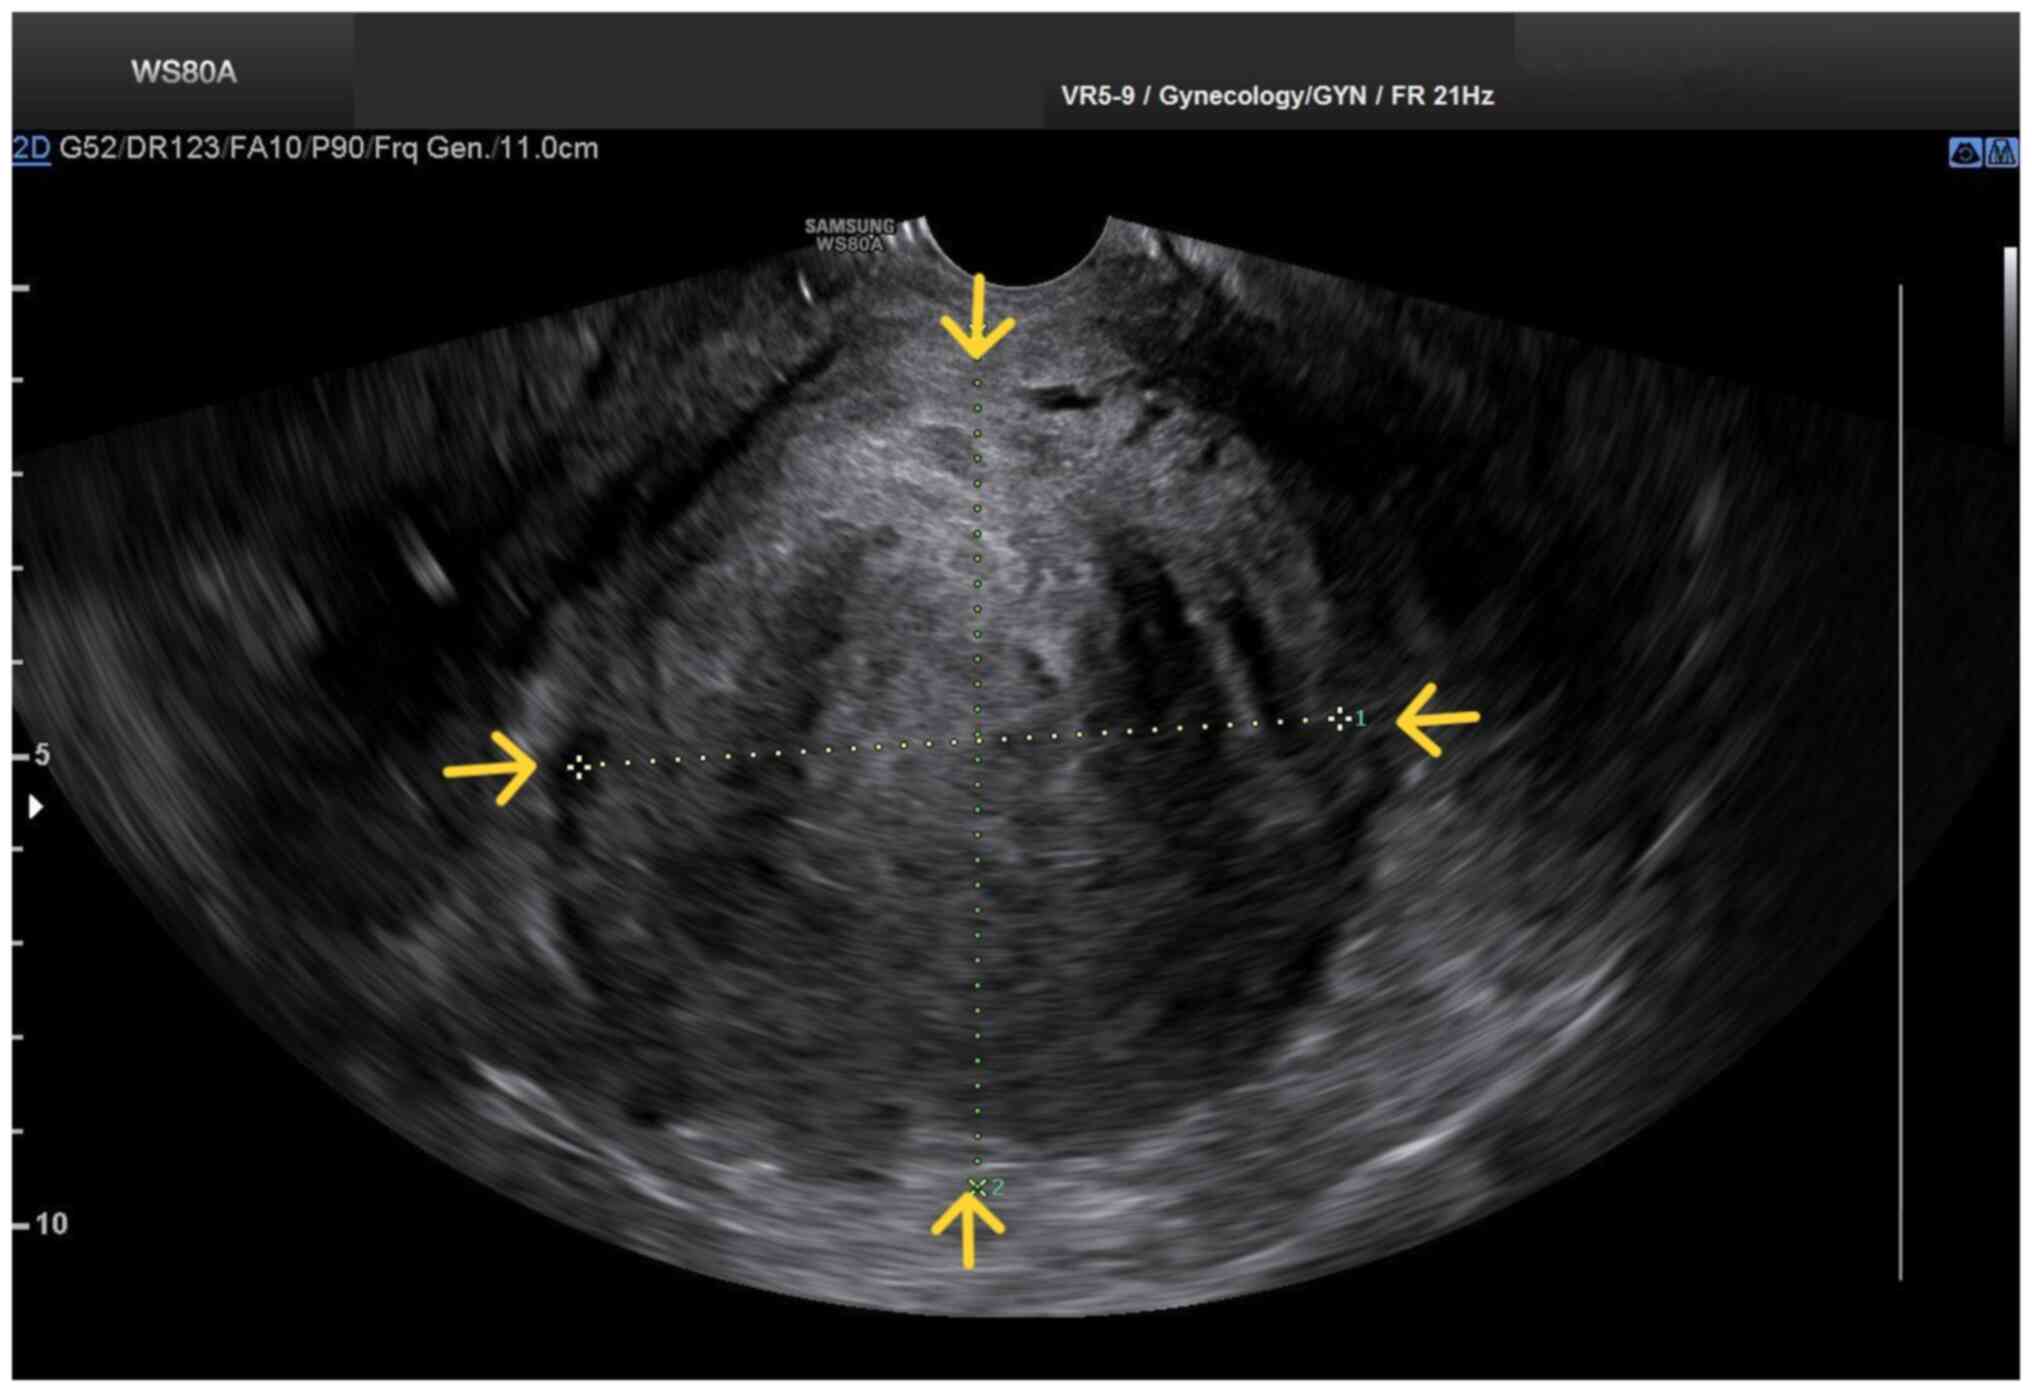

Figure 2

Transvaginal ultrasound image of a large prolapsed pedunculated submucosal uterine leiomyoma: The pelvic mass is clearly depicted (yellow arrows), without clear imaging of the adjacent anatomical structures.

Upon a gynecological examination and upon the inspection of the vagina with a speculum, the cervix was not visible. In the upper third of the vagina, in the anatomical position of the cervix, a large solid mass was observed; the position of the external cervical os could not be clearly identified by visual inspection or palpation (Fig. 1). The transvaginal ultrasonographic findings were inconclusive. The scan detected the presence of a large well-circumscribed mass, with a maximum diameter of 10 cm, at the anatomical position of the cervix, raising suspicion of an intracervical leiomyoma (Fig. 2). A renal ultrasound revealed the bilateral dilatation of the pelvicalyceal system and the ipsilateral proximal ureter (Fig. 3). Furthermore, a computed tomography scan was performed, which revealed significant bladder dilatation and internal non-homogeneity of the cervical canal throughout its entire length, measuring 105x95x90 mm. This lesion caused the thinning of the external wall of the cervix and anterior displacement of the bladder. At the same time, it exerted compression on the posterior wall of the bladder, and malignancy arising from the cervix could not be excluded (Fig. 4). Additionally, computed tomography confirmed the dilatation of the pelvicalyceal system bilaterally up to the ureterovesical junction, accompanied by localized renal cortical thinning and lobulated contour of the left kidney. Magnetic resonance imaging was performed to further elucidate the findings of computed tomography. Magnetic resonance imaging revealed marked bladder distention with internal non-homogeneity of the cervical canal and the presence of a lobulated lesion that protruded intracanal with dimensions of 100x85x105 mm (Fig. 5). This finding was attributed to a large intracervical leiomyoma, strongly ruling out the possibility of cervical malignancy. The levels of tumor markers, namely carcinoembryonic antigen, cancer antigen 125, cancer antigen 15-3 and cancer antigen 19-9 were within the normal range.

Imaging plays a crucial role in the pre-operative diagnosis of patients with prolapsed pedunculated submucosal leiomyoma. In these patients, computed tomography can distinctly reveal a well-circumscribed pelvic mass with mixed echogenicity, incorporating degenerative changes and necrotic lesions, thereby facilitating an early and accurate diagnosis (13). Magnetic resonance imaging can also provide critical imaging information regarding the precise location of the leiomyoma in relation to the myometrium, the degree of vascularization and the position of adjacent anatomical structures, significantly contributing to the planning of optimal surgery (14,15). In the patient in the present study, however, the pre-operative imaging diagnosis of prolapsed pedunculated submucosal uterine leiomyoma posed significant challenges. None of the imaging modalities used (ultrasound, computed tomography or magnetic resonance imaging) was able to pre-operatively establish the diagnosis of prolapsed pedunculated submucosal uterine leiomyoma. The ultrasound initially misdiagnosed a large intracervical fibroid. Computed tomography confirmed the ultrasound findings, but could not exclude the possibility of cervical malignancy. Magnetic resonance imaging incorrectly confirmed the diagnosis of intracervical fibroid and almost ruled out the possibility of cervical malignancy.